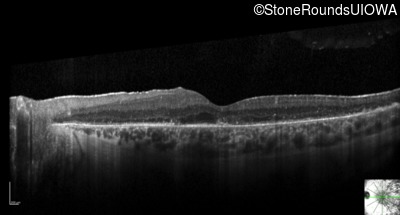

Optical Coherence Tomography - Right - 20/32 -1

Exemplar / OCT Stack

OCT Stack